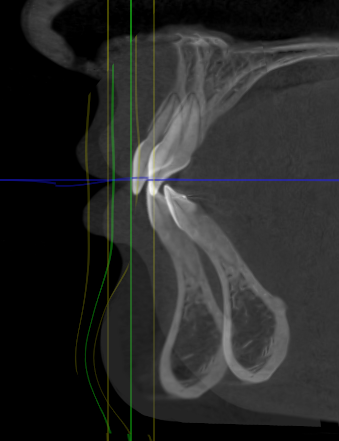

I played with my cbct a bit and this is something close to what I'm going to get.

4.4mm on maxilla and approx. 15mm on the lower

However, to pass all the convexities in a chad tier i would need 8.8mm on maxilla and 20mm on my lower jaw (likely 12/13mm lj + 8/7mm genio)

Of course, im also getting some counter clockwise rotation